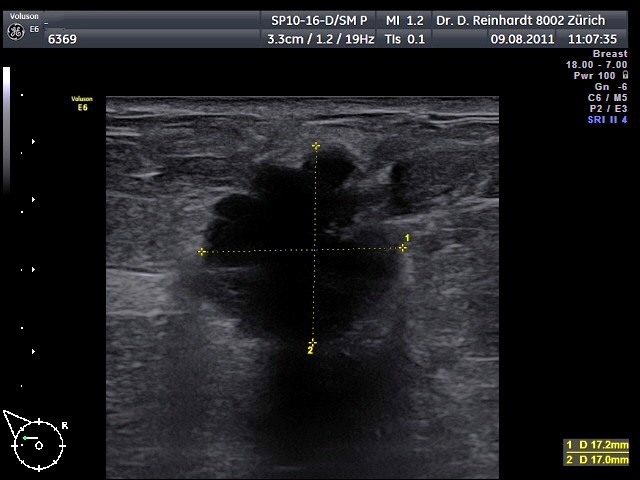

Verdacht auf Brustkrebs